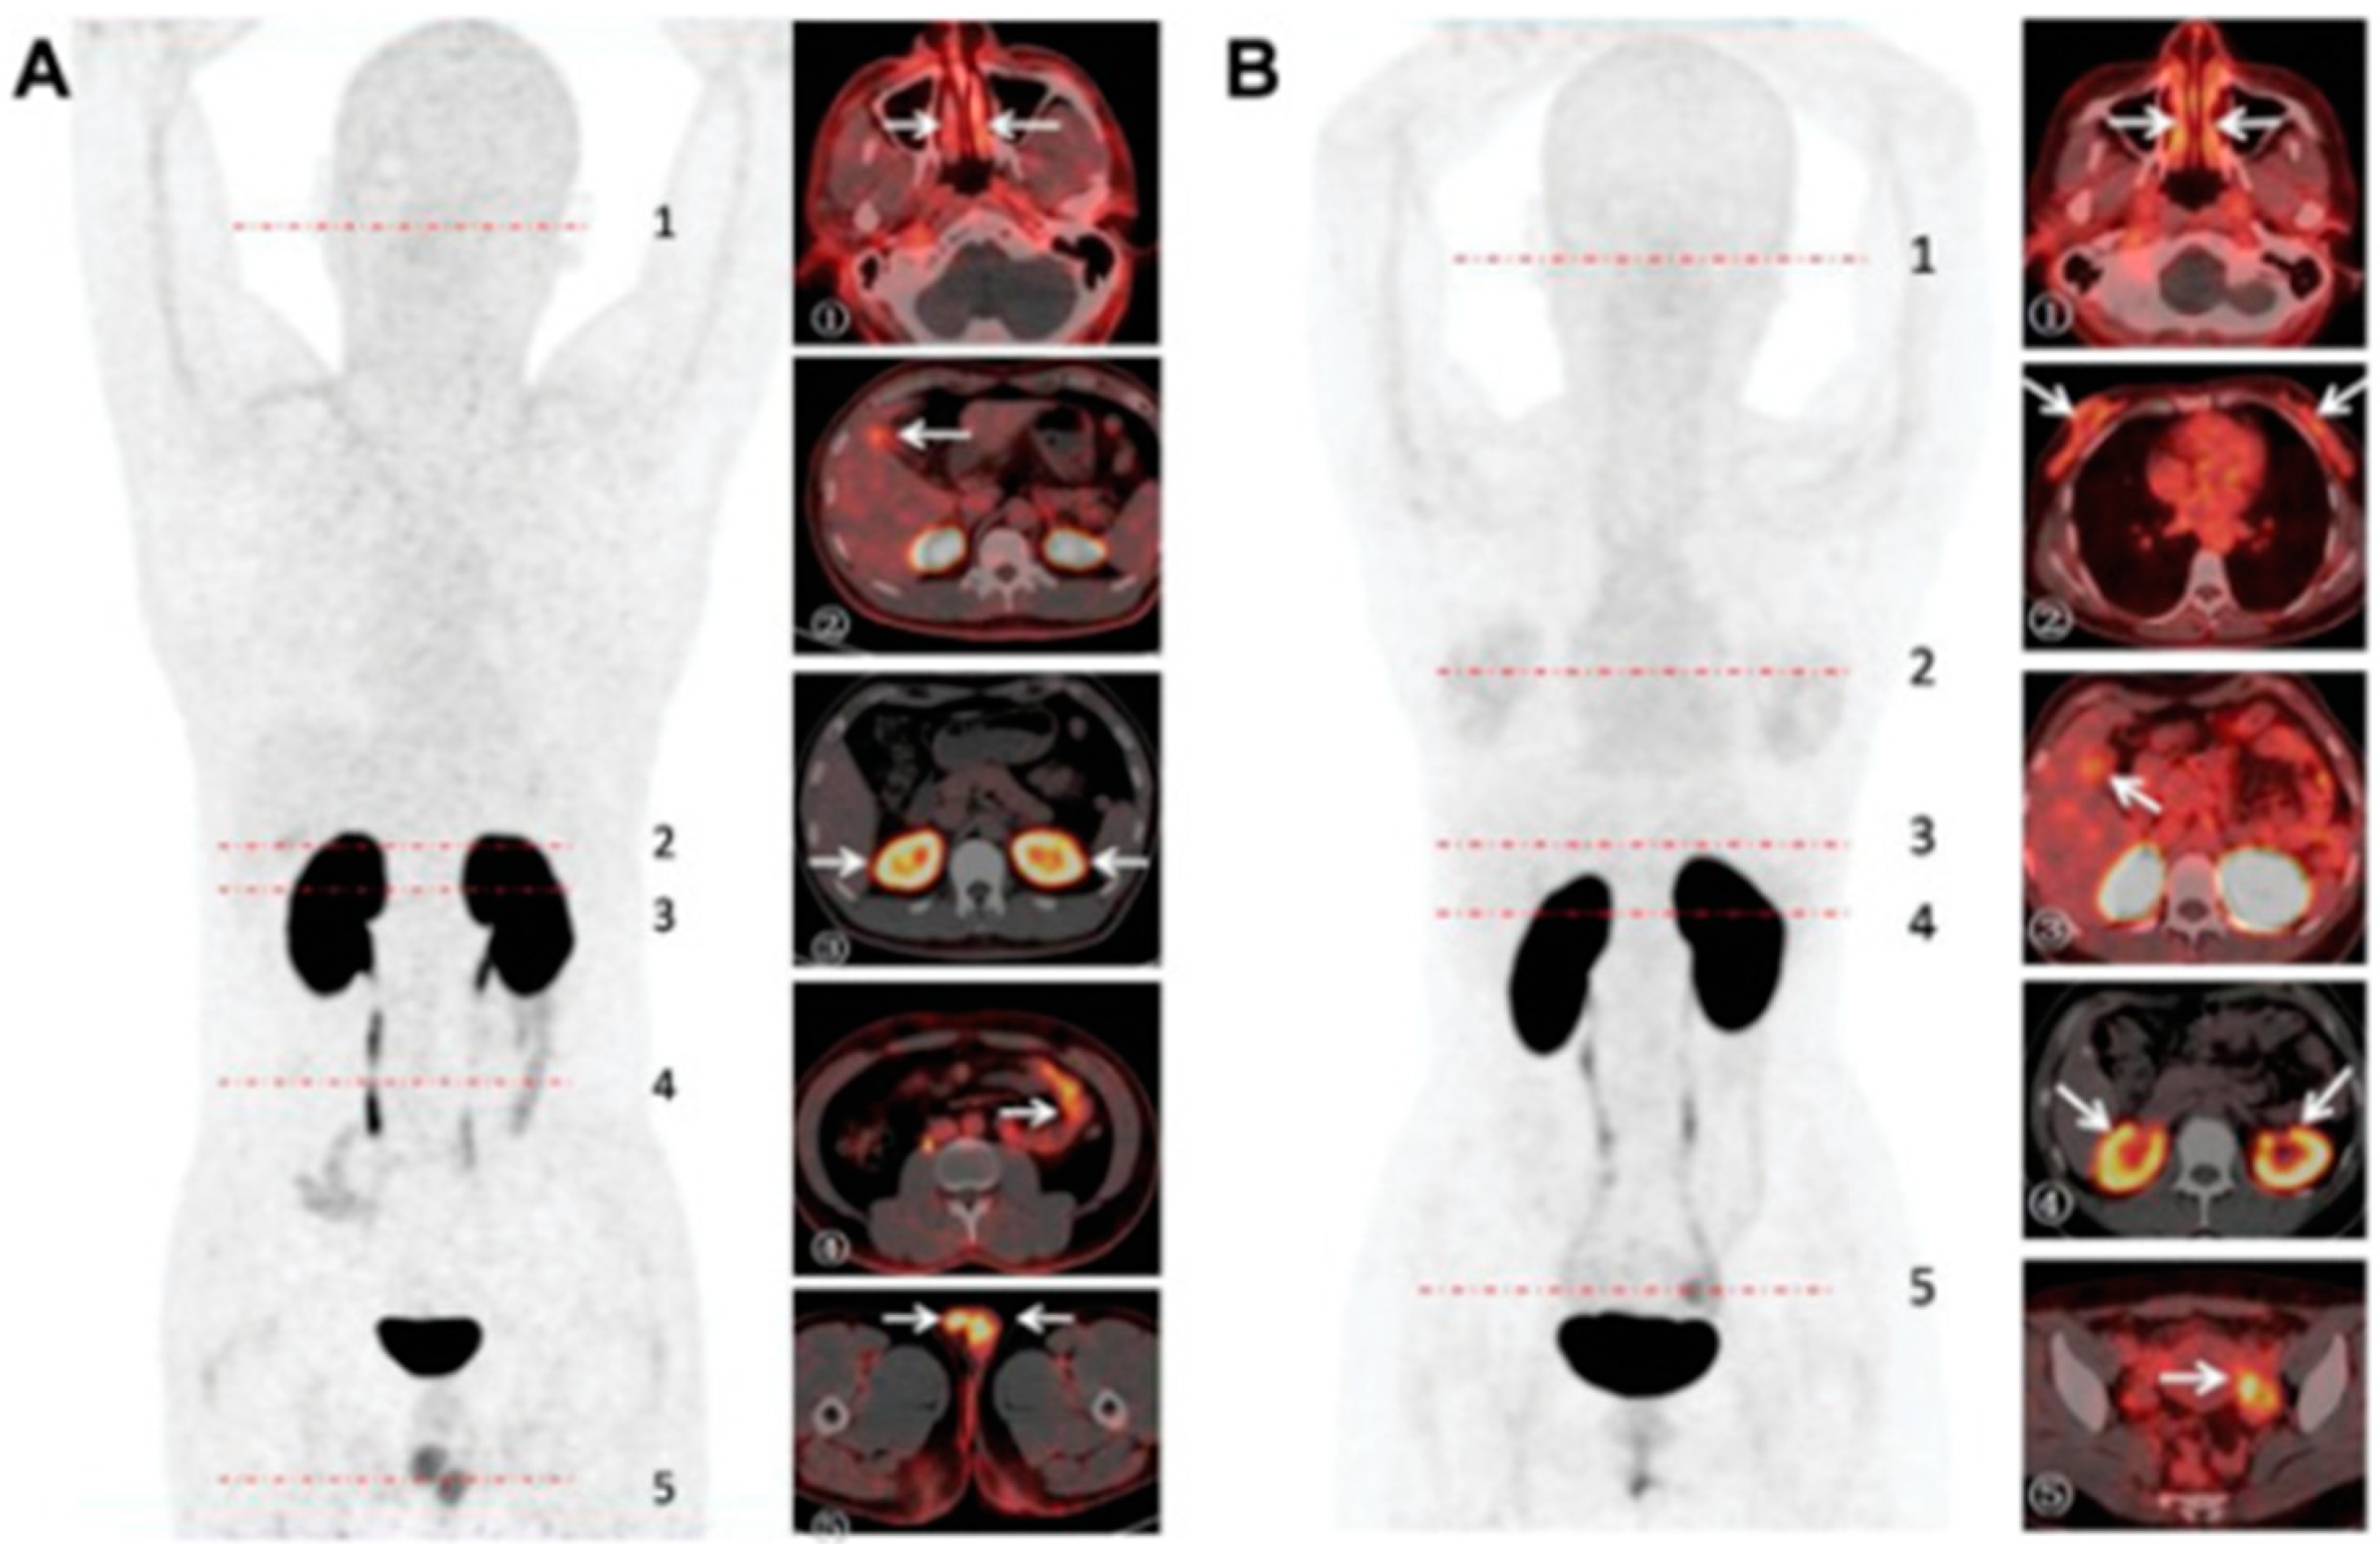

5.2. ACE2 Imaging with DX600

- Zhu, H.; Zhang, H.; Zhou, N.; Ding, J.; Jiang, J.; Liu, T.; Liu, Z.; Wang, F.; Zhang, Q.; Zhang, Z.; et al. Molecular PET/CT Profiling of ACE2 Expression In Vivo: Implications for Infection and Outcome from SARS-CoV-2. Adv. Sci. 2021, 8, e2100965. [Google Scholar] [CrossRef]

- Ren, F.; Jiang, H.; Shi, L.; Zhang, L.; Li, X.; Lu, Q.; Li, Q. (68)Ga-cyc-DX600 PET/CT in ACE2-targeted tumor imaging. Eur. J. Nucl. Med. Mol. Imaging 2023, 50, 2056–2067. [Google Scholar] [CrossRef]